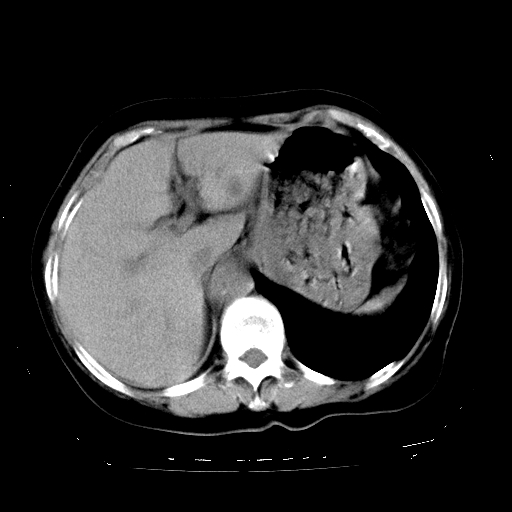

标题: CT23991:女,72岁,咳嗽、憋气一周。 [打印本页]

女,72岁,咳嗽、憋气一周,十年前曾患肺结核及胸膜结核。

1.右侧损毁肺伴胸膜钙化,2.左肺小结节灶,良性可能大,注意复查。3.肝脏左叶囊肿。4.先天性一侧肺不发育待出外(右侧胸廓无明显塌陷)。对比原片应该非常有帮助。

支持楼上,肝脏多发囊肿